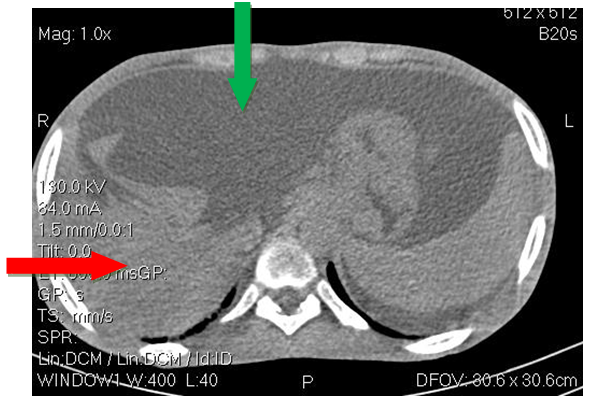

He was a 23-year-old male with no previous history, including no ethylo-smoking or cardiovascular pathology, admitted in November 2018 for diffuse, atrocious, diffuse abdominal pain, sudden twisting associated with vomiting and a cessation of materials and gases. The physical examination revealed an abdominal meteorism. The unprepared abdomen radiograph (ASP) had objectified hydro-aerobic levels wider than high. Acute intestinal obstruction by volvulus of the hail was suspected. He underwent an emergency laparotomy which revealed acute mesenteric ischemia for which an ileal resection of approximately 1.5m with terminal ileo-ileal anastomosis was performed. The postoperative effects were marked by the recurrence of the mesenteric infarction clinical presentation one week later requiring surgical resection with a new 50cm ileum resection and terminal ileo-ileal anastomosis. The evolution was marked by the appearance of an alteration of the general state (performance status index at 2 according to the World Health Organization); with anorexia, significant weight loss, malabsorption diarrhea made of liquid stools, at least 10/day containing food residues; with the occurrence of ascites whose puncture shows a liquid low in protein at 0.59g/l. The patient was then transferred to the gastroenterology department for further assessment. On physical examination the patient had an impaired general condition with a BMI of 16.4Kg/m2. The abdomen was enlarged (Figure 1) with signs of portal hypertension (collateral venous circulation, splenomegaly and ascites). Biologically, he had hepatocellular insufficiency (low prothrombin (TP) rate at 49.2%, low albuminemia at 30.7g/l). The electrophoresis of the proteins objectified a biological inflammation syndrome (hypoalbuminemia at 30.7g/l and hypergammaglobulinemia at 37g/l). Esophageal endoscopy noted the presence of grade II esophageal varix without red sign with intense portal hypertension gastropathy. Abdominal CT scans (Figures 2A–C) showed atrophic liver, ascites, splenomegaly and intra-abdominal collateral venous circulation. Viral serologies B (HBsAg and total anti HBc antibodies) and C as well as human immunodeficiency virus (HIV) were negative. Lipid and blood sugar levels were normal. The cardiological consultation with electrocardiogram and cardiac ultrasound did not reveal any pathology. A thrombophilia check-up (antithrombin deficiency, protein C and S deficiency, Antiphospholipid antibody, factor V Leiden mutation, prothrombin gene mutation) was requested remotely from the ischemic episode, but not yet performed due to a lack of resources. Symptomatic treatment with analgesics (non-opioid and opioids), evacuation of ascites with diuretics, prevention of rupture of esophageal varices by beta-blocker, slowing of transit (loperamide) and nutritional assistance with oral dietary supplements and iron and calcium supplementation have been instituted. The evolution under this treatment was favourable. The patient was discharged with regular follow-up for screening for hepatocellular carcinoma.

Figure 2A Abdominal CT scan showing atrophic liver and ascites.